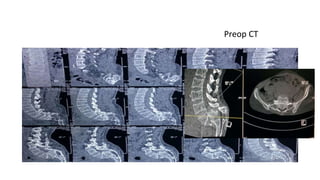

Preop CT

PI= 40◦ PT= 20◦ SS=20◦ C7 PL falls behind the femoral heads SS PIPT C7PL Preop Sagittal Profile X Ray